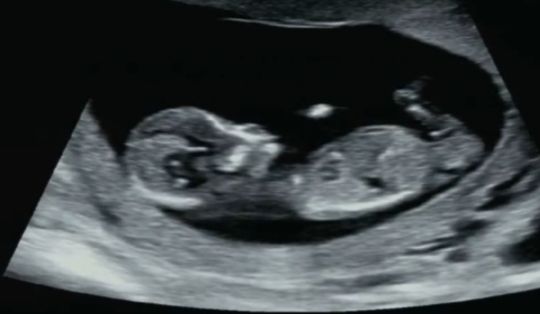

성별 참견 부탁드려요🙏

ㅠㅠㅠㅠ제발...!!!

초음파 사진을 올리면 AI가 무료로 예측해줘요